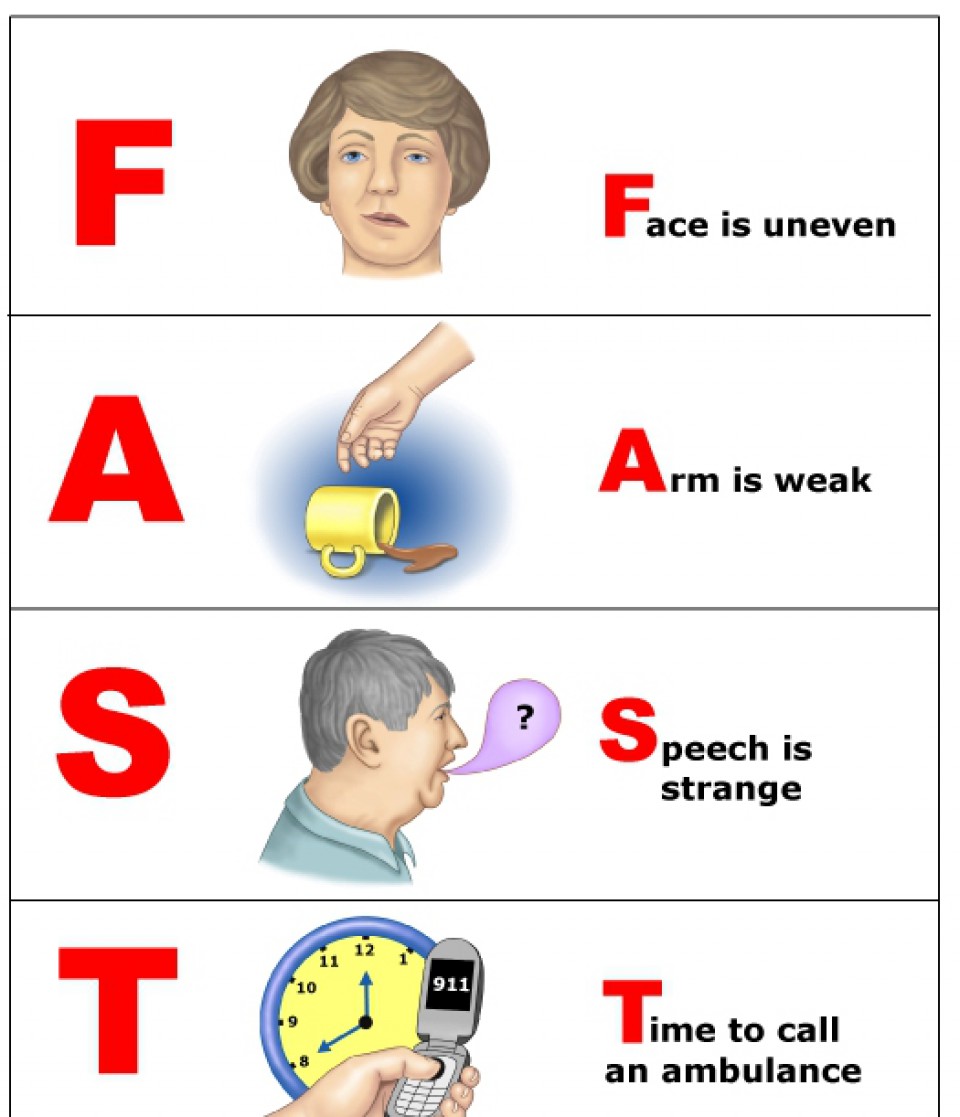

Bez obzira na vrstu moždanog udara simptomi su slični: poremećaj govora, oduzetost ekstremiteta, otežan ili nemoguć hod, vrtoglavica, glavobolja, povraćanje, poremećaj gutanja, duple slike, trnjenje, a u najtežim slučajevima poremećaj svijesti sve do kome.

Imajući sve ovo u vidu jedini ispravan odgovor na Vaše pitanje jeste da se ljekru treba javiti ODMAH, čim se uoče simptomi koji mogu ukazivati na moždani udar.

U cilju ujednačavanja kriterijuma za liječenje moždanog udara 2012. godine, pod pokroviteljstvom Ministrstva zdravlja smo po ugledu na razvijene zemlje napisali Nacionalne smjernice dobre kliničke prakseza akutni ishemijski moždani udar koje se nalaze na internet stranici Ministrastva zdravlja, a u okviru kampanje koja je namijenjena edukaciji stanovništva za brzo prepoznavanje moždanog udara napisala sam boršuru „Prepoznajte moždani udar- svaki minut je važan“.